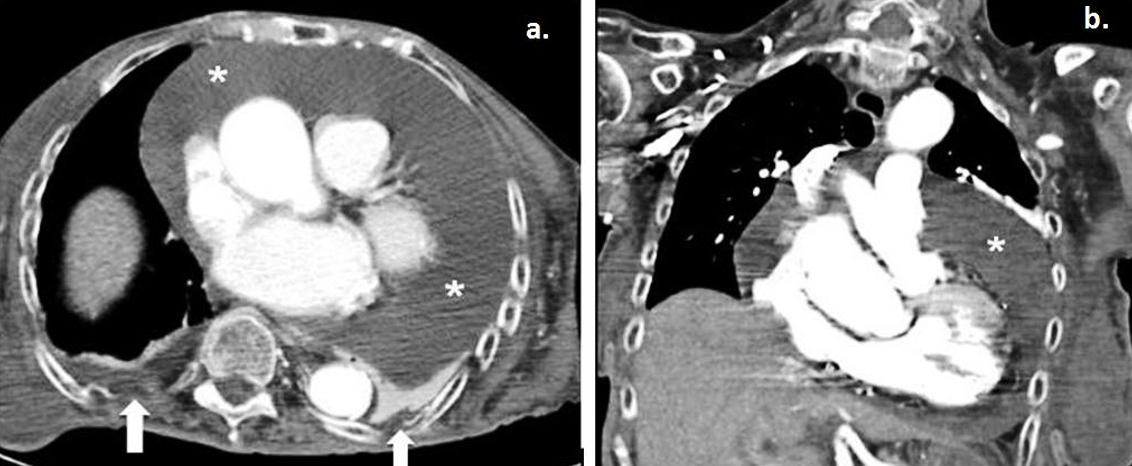

A new echocardiograph and chest CT (Fig2a,b) were performed, revealing a massive pericardial effusion with no evidence of aortic dissection or neoplastic pericardial involvement and without echocardiographic findings of cardiac tamponade. According to the ESC position statement on triage strategy for pericardial diseases5, the patient had a score of 5 and, despite the absence of cardiac tamponade, a pericardiocentesis was performed after 48 hours. During the procedure, 1070 mL of pericardial fluid was drained and analysis showed exudate. Cytological examination was negative for malignancy. Pericardial fluid culture was negative. Consequently, subclinical hypothyroidism was considered the cause of the pericardial effusion and the patient was treated with 125 µg levothyroxine orally OD.

Figure 2: a. Axial contrast-enhanced computed tomography and coronal maximum intensity projection–reconstruction during the patient’s hospitalisation revealed a large global pericardial effusion (*). b. Small bilateral pleural effusions are also noted (white arrows).